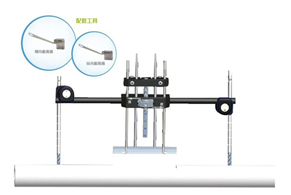

橫向骨搬移外固定支架彩頁

發布時間:2019-11-07